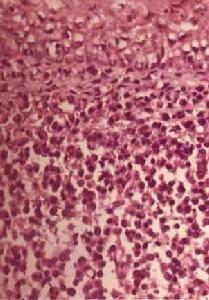

結膜細胞1.結膜細胞學 結膜刮片有助於變應性眼病的診斷正常人結膜不含有嗜酸性粒細胞或嗜酸性顆粒。因此,在結膜刮片的Giemsa染色中如發現嗜酸性粒細胞或嗜酸性顆粒,將提示局部有變應性過程發生。結膜活檢組織在電鏡下發現有肥大細胞、嗜鹼性粒細胞、嗜酸性粒細胞和(或)嗜酸性粒細胞顆粒,也具有相同的臨床價值。利用電鏡技術可以對肥大細胞及其顆粒進行鑑定和計數。在VKC患者,許多肥大細胞發生了廣泛性的脫顆粒,從而使其在光鏡下難以辨認。